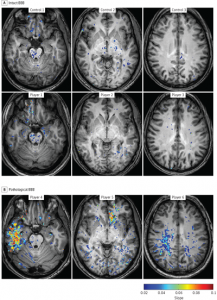

Confronto tra la permeabilità della barriera ematoencefalica (BBB) tra giocatori di football americano (A) e un gruppo di controllo (B). I giocatori del gruppo con patologia della BBB (B) presentano lesioni BBB focali in diverse aree corticali, compresi i lobi temporale (giocatore 4), frontale (giocatore 5) e parietale (giocatore 6). Sono coinvolte sia la sostanza grigia che quella bianca.Friedman spiega anche che non tutti i giocatori hanno mostrato la patologia. Ciò indica che i lievi eventi commozionali ripetuti potrebbero avere un impatto diverso su alcuni giocatori da quello di altri. Questo livello di diagnosi dei singoli giocatori è in grado di fornire la base del processo decisionale più razionale per "tornare a giocare" sia per i professionisti che per i dilettanti di ogni età. "In generale, i giocatori tornano al gioco molto prima che sia completata la guarigione fisica del cervello, fatto che potrebbe esacerbare la possibilità di danni al cervello più avanti nella vita", dice Friedman.